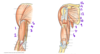

Which nerve supplies the structures in purple (labeled #4)?

Medial cutaneous nerve of the forearm

(A branch from the brachial plexus)

Which vein is labeled by #2?

Cephalic vein

(Empties into the axillary vein)

Which structure is labeled by #5?

Head of the ulna